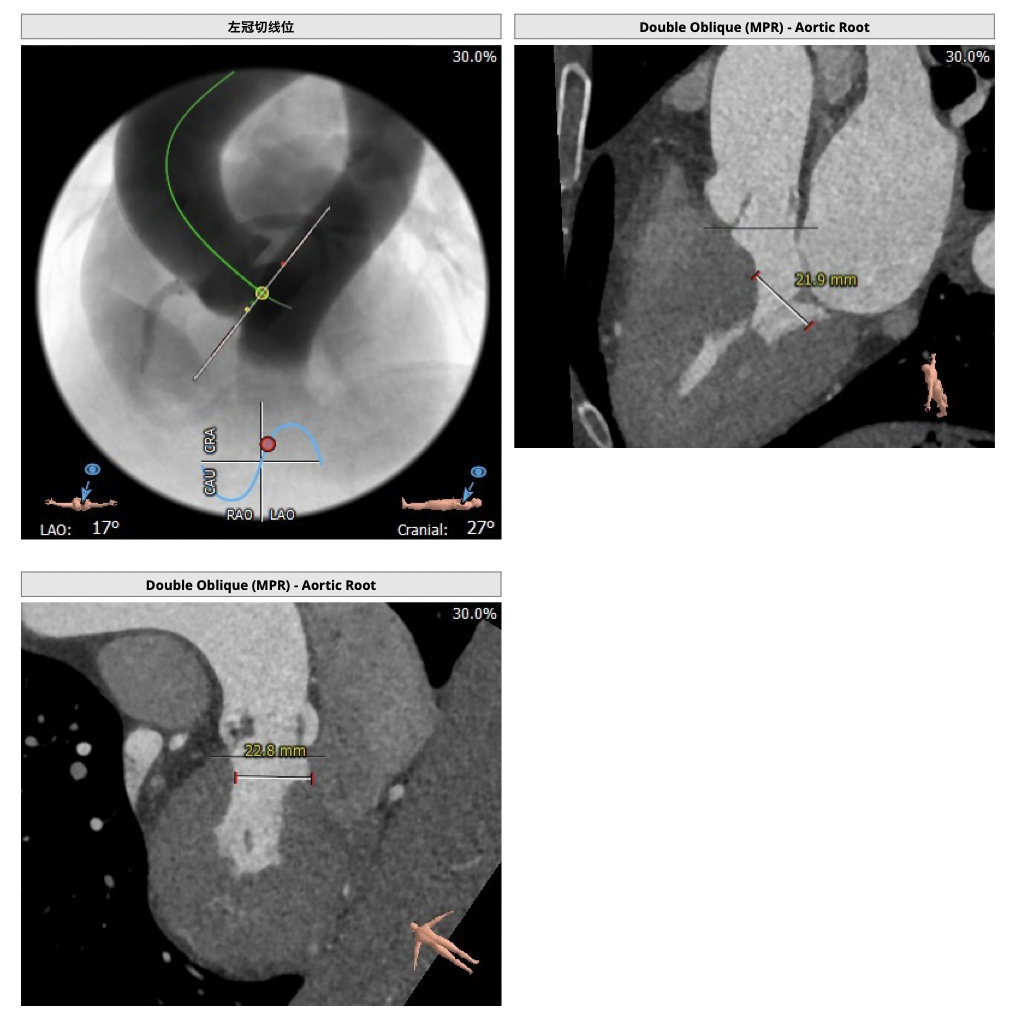

*心脏角度为57°,横位心,输送器过瓣难度增加,瓣膜植入同轴性差,瓣膜释放更易移位,增加了操作的难度;

经分析研判,拟从右侧股动脉穿刺入路,使用20mm球囊预扩,采取downsize手术策略,选用L23号的VenusA-Valve瓣膜,因患者为横位心,瓣膜释放同轴性差,容易发生移位,故采用VenusA-Plus可回收输送系统确保瓣膜的稳定释放,瓣膜释放后结合造影和超声情况,决定是否后扩。

根部造影